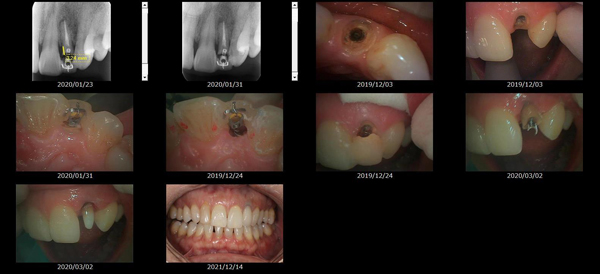

救歯MTMについて

虫歯が大きくて残せない歯、転倒などの事故により歯が根の深いとこで折れてしまったなどで、抜かざるを得ない歯を、骨の中に埋まっている健全な根を、骨の上に矯正的に引き上げることで、その歯を抜かず温存、救歯できる可能性のある治療方法です。

救歯治療と審美性の両立

学会発表ポスター